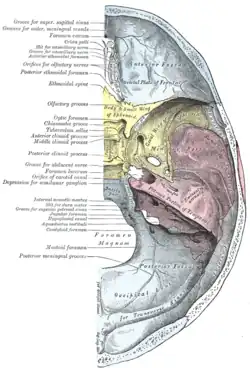

Paredes da cavidade nasal esquerda. Parede lateral da cavidade nasal.

Parede lateral da cavidade nasal.